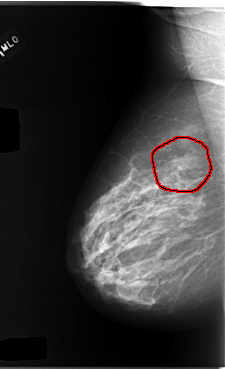

C_0095_1.RIGHT_MLO

RIGHT_MLO LINES 5904 PIXELS_PER_LINE 3600 BITS_PER_PIXEL 12 RESOLUTION 50 OVERLAY

FILE: C_0095_1.RIGHT_MLO.OVERLAY

TOTAL_ABNORMALITIES 1

ABNORMALITY 1

LESION_TYPE MASS SHAPE IRREGULAR MARGINS SPICULATED

ASSESSMENT 4

SUBTLETY 4

PATHOLOGY MALIGNANT

TOTAL_OUTLINES 1

BOUNDARY